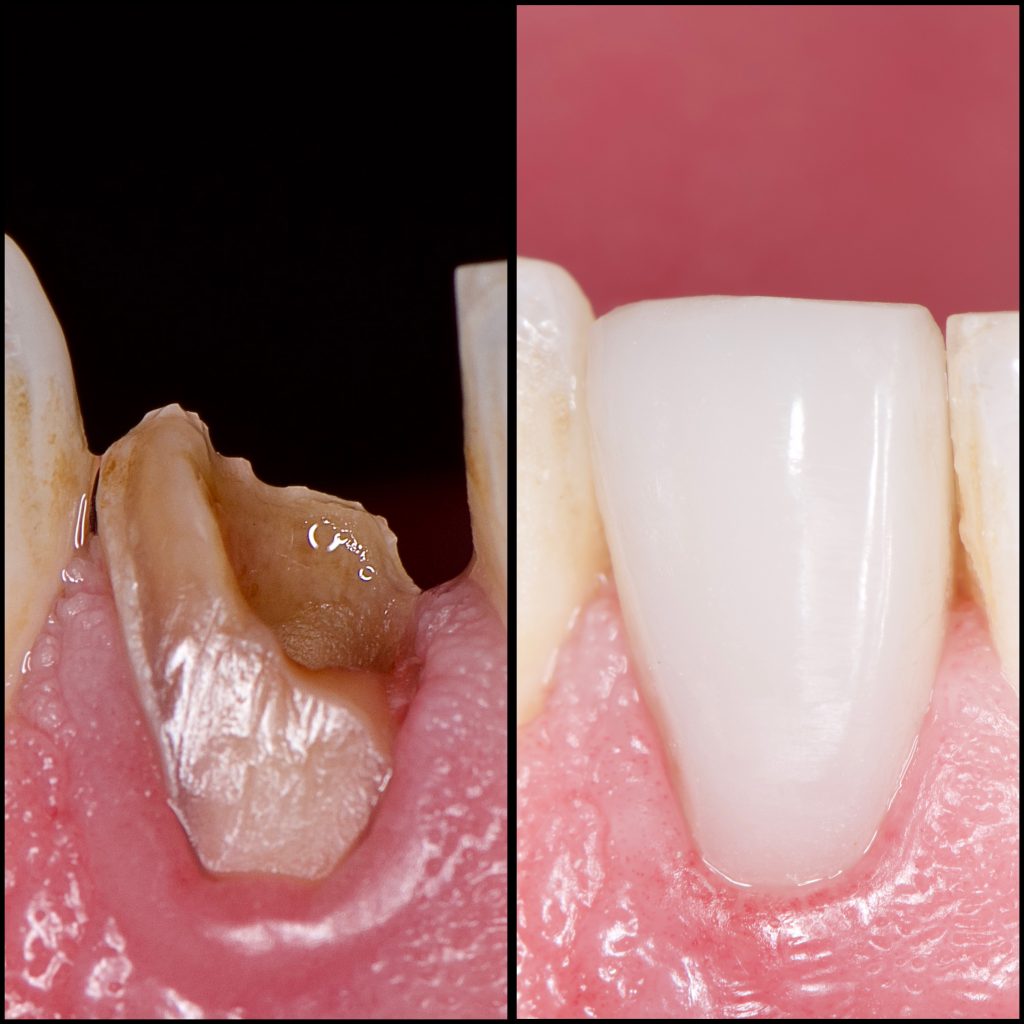

25 years old male had sport injury long period ago.

He Visited us because of pain in his fractured lower anterior tooth

Fractured Lower lateral incisor was necrotic and had periapical lesion as seen in X-ray

– Direct composite restoration, layering technique

1 month Follow up